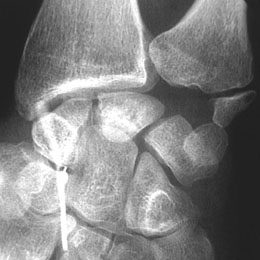

A - Arthrographie de la médio-carpienne - vue initiale : Cliché avant injection.

B - Arthrographie de la médio-carpienne - vue précoce : Pénétration de contraste à travers un defect du ligament luno-triquetral.

Defect communicant du ligament luno-triquetral.